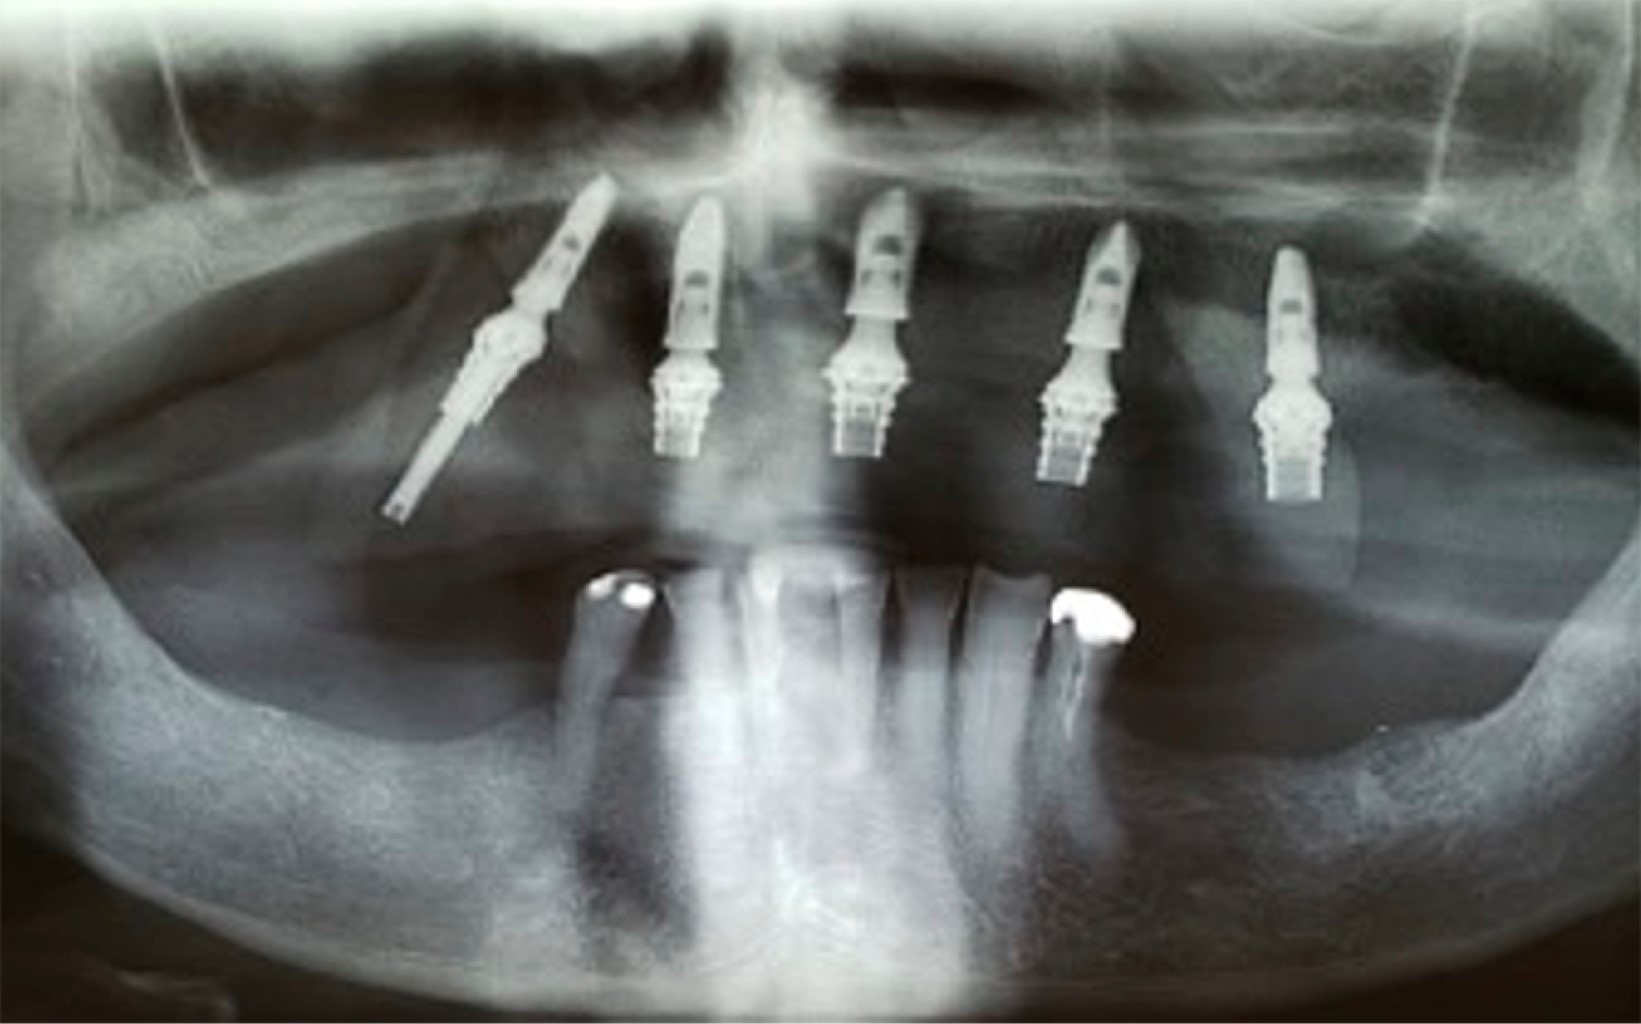

El leiomiosarcoma es un tipo de cáncer que se origina en las células musculares lisas del útero, el tracto gastrointestinal y otros tejidos blandos. La rara aparición del leiomiosarcoma en la cavidad oral se ha correlacionado con la escasez de estructuras musculares lisas en esta localización. Se trata de un tumor de tejidos blandos raro y agresivo que representa aproximadamente 5-10% de todos los sarcomas de tejidos blandos, y sólo 3% de estos tumores se producen en la región de la cabeza y el cuello. El diagnóstico diferencial puede ser problemático. El aspecto físico puede confundirse con afecciones no malignas. El diagnóstico diferencial clínico de la lesión incluye los tumores glandulares (adenoma pleomórfico, carcinoma mucoepidermoide y carcinoma adenoide quístico) y los tumores mesenquimales. Relatamos un caso de leiomiosarcoma maxilar en un paciente de 86 años que fue sometido a una resección tumoral y tuvo como complicación la necrosis casi completa del retallo quirúrgico. Gracias a la terapia con láser, logramos la curación completa del colgajo y el implante y la rehabilitación dental con carga inmediata.

Figura 2